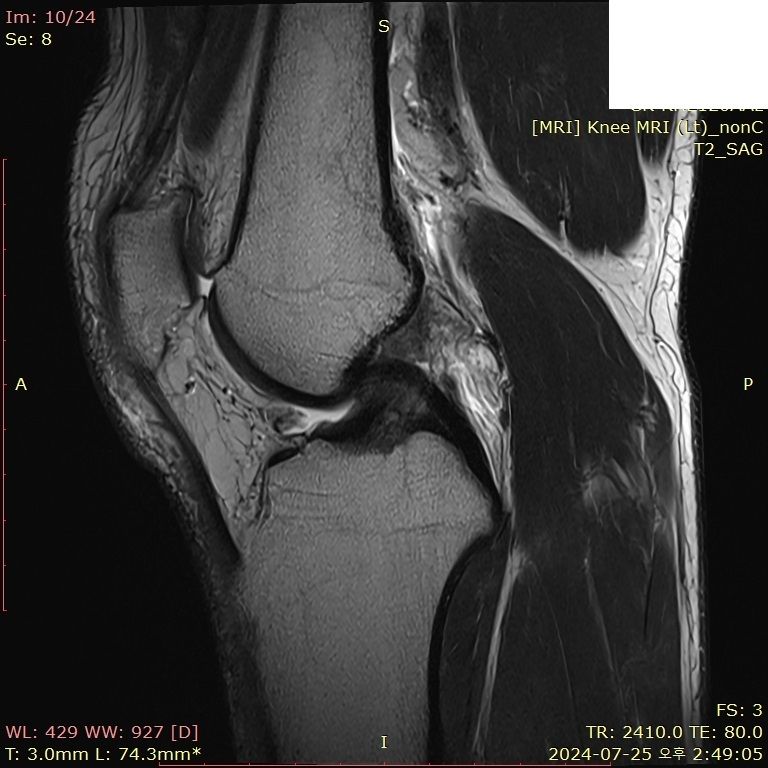

무릎 부딪혔는데 mri 한번 봐주시면 감사하겠습니다..

뛰다가 넘어졌습니다.. 예전에는 무릎이 부어도 병원 안 갔는데, 최근에는 중요성을 알아서 미리미리 검진 받자는 의미로 갔다왔습니다

• 2번 째 사진

보여주신 MRI만 보면 전방, 후방 십자인대 손상이 의심되지 않습니다.